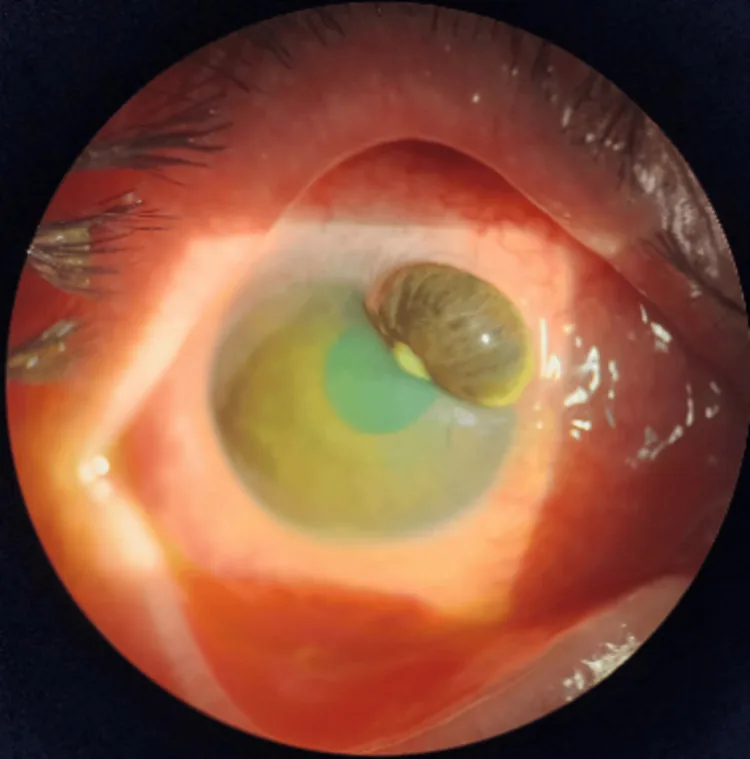

角膜実質菲薄化・穿孔リスク

Section titled “角膜実質菲薄化・穿孔リスク”経口ドキシサイクリンは粘膜類天疱瘡阻害により角膜実質菲薄化に対抗する可能性があるが、感染性角膜炎での使用データは限定的である3)。

Section titled “粘膜類天疱瘡阻害と角膜保護”ドキシサイクリンは粘膜類天疱瘡-9を直接的に阻害するとともに、MAPKシグナルの活性化を抑制し、角膜上皮における炎症性サイトカインの発現を減少させることが実験的ドライアイモデルで示されている1)。

経口ドキシサイクリン、局所N-アセチルシステイン、メドロキシプロゲステロンはいずれも粘膜類天疱瘡阻害作用を有し、遷延性上皮欠損や実質菲薄化に対する治療選択肢として検討されてきた。ただし、in vivoでの効果の評価は特に構造化された二重盲検の設定では困難である。